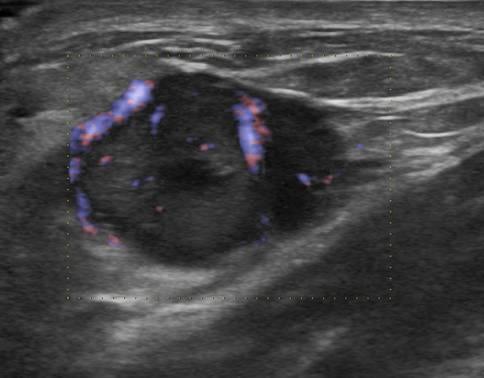

Ung thư vú

Ung thư vú - Ảnh 2

» Thông tin: Nữ giới – 54 tuổi.

» Lâm sàng: Khối tuyến vú.